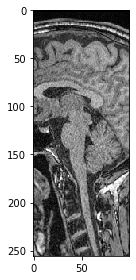

También podemos seleccionar un plano donde todos los píxeles tengan la misma posición Y. Solo necesitamos especificar que nos gustaría mantener todos los píxeles en Z usando la sintaxis :.

slice_image = image[:, 100]

imshow(slice_image)

../_images/ad292cbffaab643c3d9273781ac2d7a8cb9aeed56d351d1c201b74c79fcbef31.png